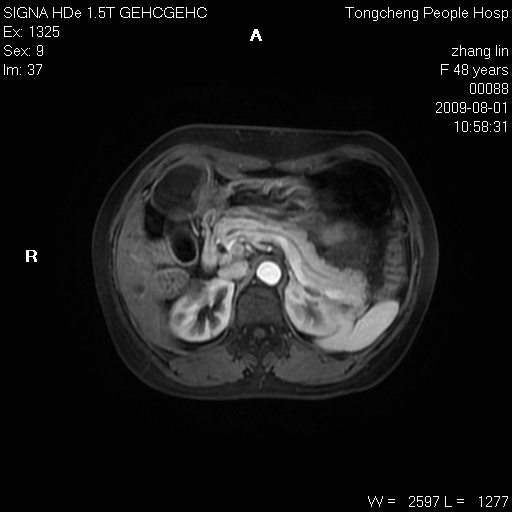

女,48岁。健康体检,彩超发现右肾占位性病变。平素健康。

临床诊断:右肾占位性病变,性质待定(囊肿?肿瘤?)。

上中腹部mr平扫+增强扫描,图像如下:

右肾上极见一类圆形病灶,t1wi呈等信号t2wi呈等高混杂信号,三期增强无强化,边界清---考虑囊肿出血。

同反相位均表现为等信号,病变无强化,考虑含蛋白的囊肿可能,弥散加权相或许有些帮助,